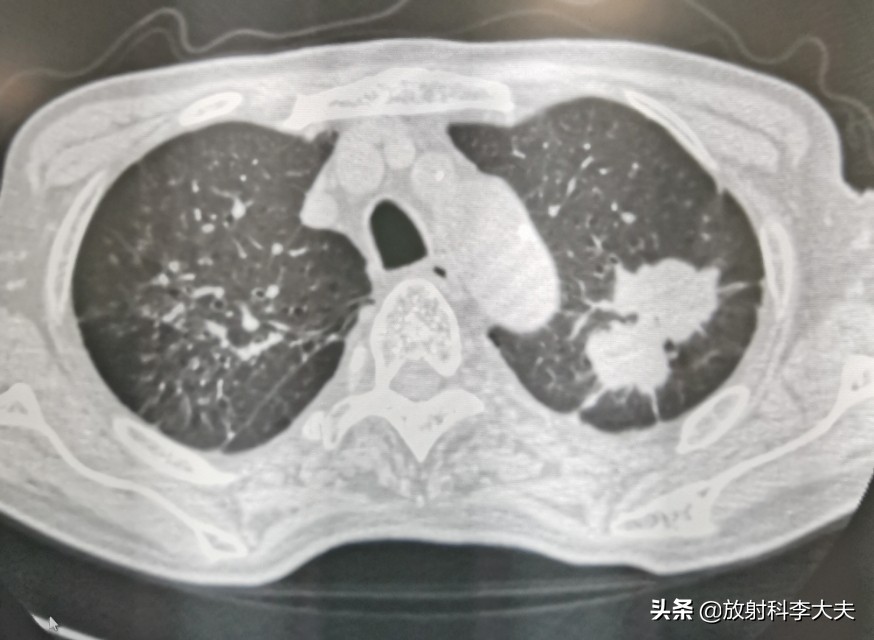

双肺多发的病灶,有的已经钙化,陈旧的结核灶。但是,左肺上叶一个哑铃形状的病变,引起重视。

左肺上叶病变可见分叶,尖后段支气管欠通畅。影像上考虑有肺癌的可能,但是鉴于有肺结核病史,还需要慎重考虑。